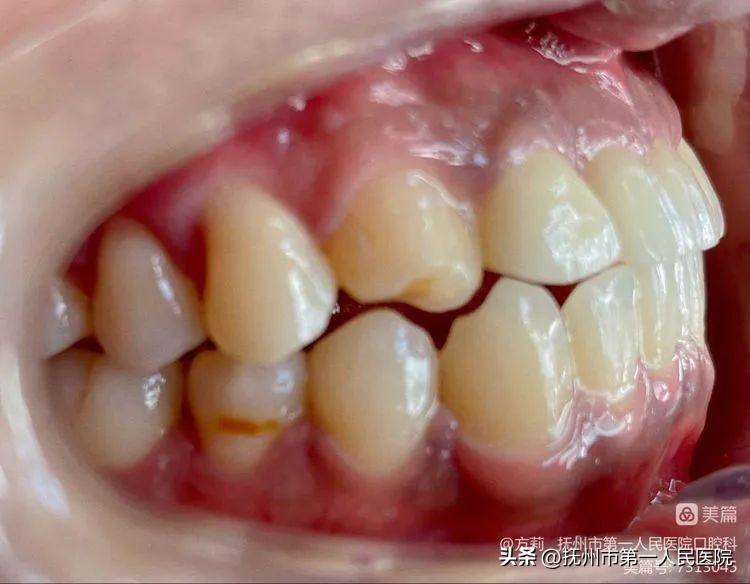

- 口内检查:

*口腔卫生情况一般;

*11、21冠根折,腭侧折断线大于龈下3mm;

*12切1/2冠折,露髓;

*13切角折断,未露髓。

患者口内侧面观!